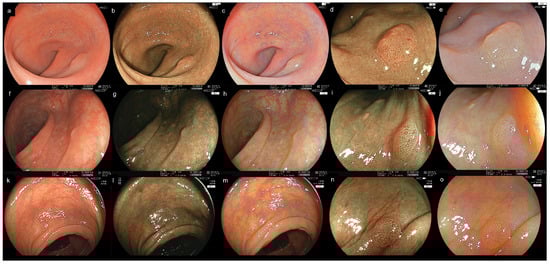

- Yoshida, N.; Hayashi, Y.; Kashida, H.; Tomita, Y.; Dohi, O.; Inoue, K.; Hirose, R.; Itoh, Y.; Okada, M.; Yoshimoto, S.; et al. Images of laser and light-emitting diode colonoscopy for comparing large colorectal lesion visibility with linked color imaging and white-light imaging. Dig. Endosc. 2022, 34, 1413–1421. [Google Scholar] [CrossRef]